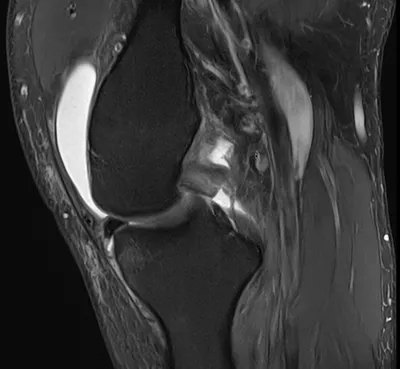

Torn PCL

MRISagittalKnee+1

2/4/2026